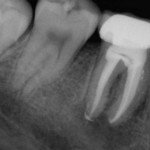

This organism contains over 3 miles of tubules (tiny fluid-filled holes in the dentin layer of each tooth). When a tooth becomes diseased to the point where it cannot be saved with a non-toxic filling or a crown, the tooth should be extracted. Period.

If a root canal is performed to “save” a dead tooth, the thousands of tubules within the tooth each become receptacles for deadly bacteria. The result is: An on-going toxic drip of bacteria such as E. Faecalis (responsible for abscess formation and destruction of tissue) into the body and its organs.

In addition, the actual root canal procedure can be the cause of infection from the get-go. A 1998 study, published in the American Academy of Periodontology, concluded that the actual root canal sites as well as the blood samples of all 26 case subjects contained anaerobic bacteria. It is a safe bet that from the minute you get that root canal (no doubt recommended and performed by your traditional local dentist), a never-ending river of bacteria starts flowing into your entire bloodstream.